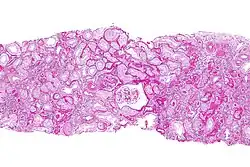

| Micrograph of chronic allograft nephropathy. PAS stain. | |

The histopathology is characterized by interstitial fibrosis, tubular atrophy, fibrotic intimal thickening of arteries and glomerulosclerosis.[2][3]